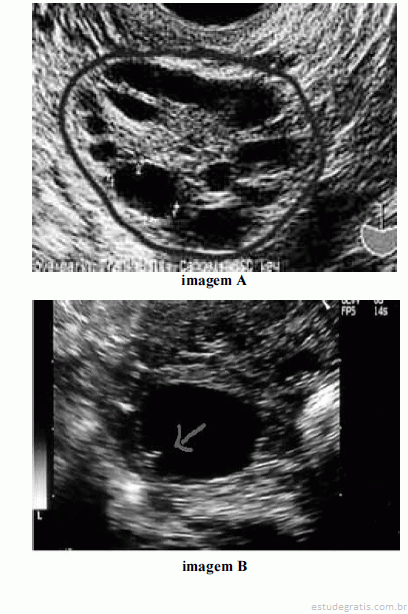

Considerando as imagens ovarianas apresentadas acima, julgue os itens a seguir.

Em ciclos ovulatórios induzidos, o crescimento folicular mostra-se independente e assincrônico, ou seja, nem sempre o maior folículo avaliado em determinada data será o maior em avaliações subsequentes.